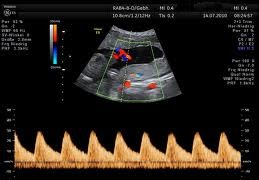

Farbdoppler-Ultraschall der Nabelschnur